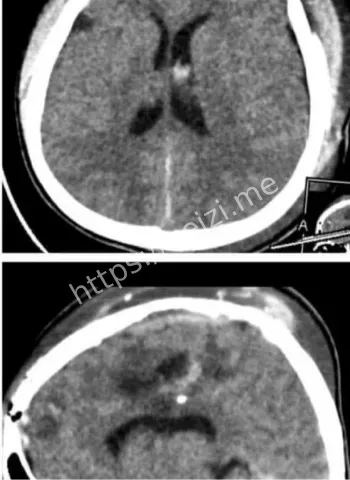

金边坤塔帕花儿童医院10月8日上演医学奇迹,一颗意外射入儿童大脑的气枪金属子弹被成功取出,手术用德国蔡司显微镜辅助,历时8小时止血止损。这起脑损伤事件引发热议,小患者恢复中,凸显儿科医疗前沿技术与医护团队的无畏精神,守护儿童生命安全。

哎呀,这事儿听起来就让人脊背发凉啊!想象一下,一个无辜的小孩儿,本来在玩耍,结果一颗该死的气枪金属子弹直奔大脑而去,造成严重出血和脑损伤。10月8日,在金边的坤塔帕花儿童医院,这帮医生们没含糊,直接上阵,启动了那场长达8小时的硬仗。不是随便切开脑袋那么简单,他们得精准定位那颗小铁疙瘩,还得一边止血一边护着脑组织不进一步坏死。整个过程像极了科幻片里的精密操作,医生们戴着放大镜似的设备,汗流浃背地干活儿。

话说回来,这颗子弹是怎么射进去的?哎,八卦起来总得挖挖根儿啊!据说这是个意外,孩子可能在附近玩气枪游戏,或者大人不小心操作失误,结果这玩意儿就钻进了小脑袋。气枪这东西,看起来像玩具,威力却不小,尤其是对小孩儿,头部中弹直接就是脑损伤大麻烦。金边这地方,热带气候,孩子们爱在户外疯玩,但安全教育跟不上,类似意外时有耳闻。这次事件一出,大家都开始反思:家长们得多盯着点啊,别让好奇心变成灾难。医院那边也没闲着,术前他们得先做一堆检查,CT、MRI啥的,全方位扫描,确保手术路径最安全。

德国蔡司显微镜辅助儿童手术技术前沿解读

哇塞,高科技这时候就闪亮登场了!坤塔帕花儿童医院这次牛就牛在用了德国最新一代的蔡司显微镜,这玩意儿放大倍数高到能看清脑神经末梢,手术精度直逼毫米级。8小时里,医生们通过这镜子,避开血管和重要脑区,一点点剥离子弹周围的组织。别小看这设备,它不光帮着看清,还能实时监控出血情况,避免二次损伤。说白了,这技术让儿童脑手术从“盲人摸象”变成“高清直播”,风险降了好几成。金边这家医院本就是儿科重镇,引进这种前沿玩意儿,简直是为东南亚小孩儿开了扇希望之窗。

手术成功了,接下来呢?小家伙的恢复路可不短啊!脑损伤这东西,后遗症可能有头晕、记忆问题啥的,但医院说手术很顺利,出血控制住了,子弹也完整取出,预后乐观。术后他们会用药护脑,还得复健训练,帮助孩子慢慢找回正常生活。想想那场景,父母守在床边,眼泪汪汪地盼着宝贝醒来,这画面太戳心了。坤塔帕花儿童医院的团队没少费心,术后监测24小时不间断,确保没并发症。黑子网用户们八卦起来,猜孩子会不会变成小超人,脑子更聪明?